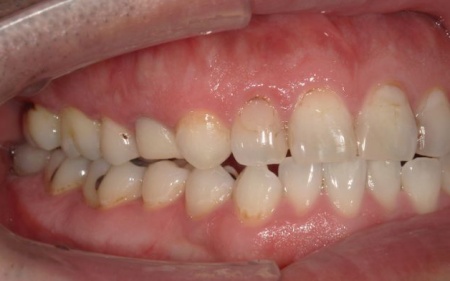

40代男性 長年放置していた虫歯や根尖性歯周炎などの口腔トラブルを全体的に治療した症例

「虫歯を長年放置してしまったので治療をしたい。また、見た目や噛み合わせの改善などを含めた、全体的な治療も行いたい」とご相談いただきました。

患者様は、10年ぶりに歯科医院を受診したとのことです。

レントゲン撮影をして詳しく検査したところ、複数の小さな虫歯が見られました。

また右上奥歯には、歯根の先に炎症が起きて膿が溜まる根尖性(こんせんせい)歯周炎が認められます。

さらに、左上奥歯(第1大臼歯)は温存が難しい状態でした。